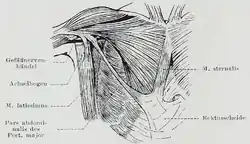

The sternalis muscle as it lies on top the pectoralis major. Sternalis muscle visible in an individual who also has an accessory abdominal pectoralis major, and an axillary arch of the latissimus dorsi.

Sternalis muscle visible in an individual who also has an accessory abdominal pectoralis major, and an axillary arch of the latissimus dorsi. Musculus sternalis seen at axial CT and volume rendering.